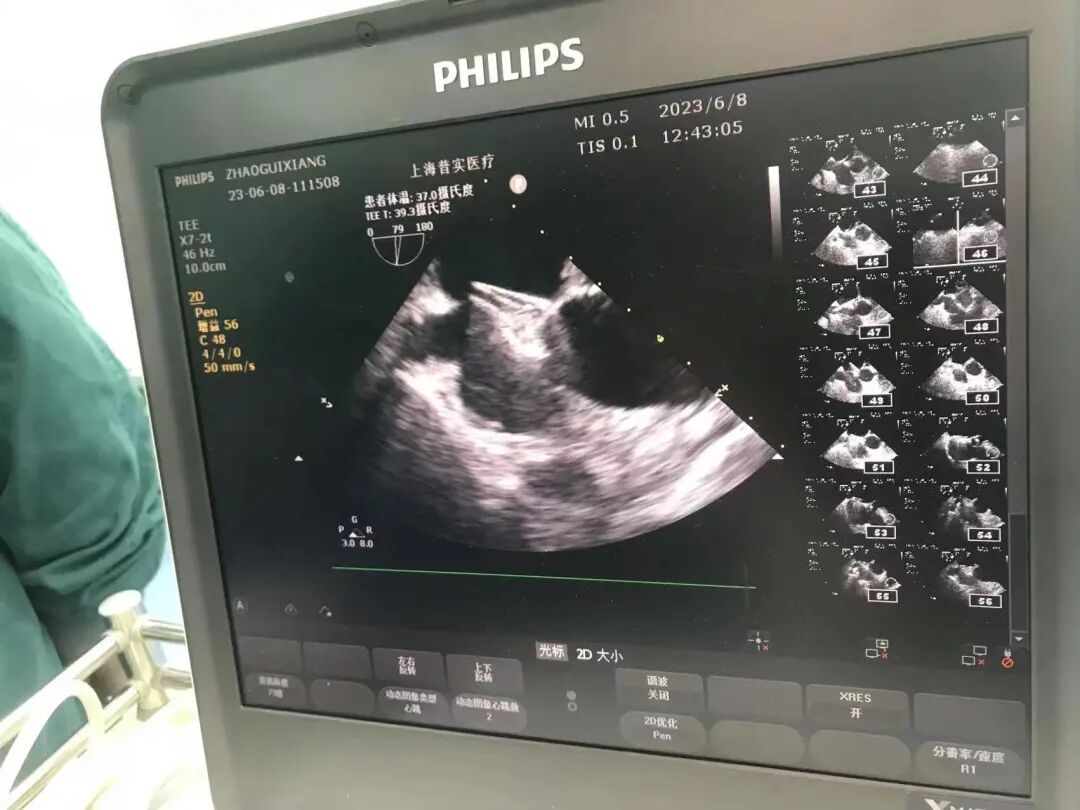

食道超声精准引导并定位